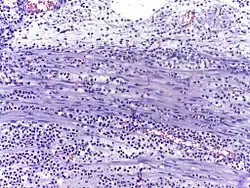

In autopsy, the presence of neutrophils in the heart or brain is one of the first signs of infarction, and is useful in the timing and diagnosis of myocardial infarction and stroke.

-

Neutrophils are seen in a myocardial infarction at approximately 12–24 hours,[67] as seen in this micrograph. -